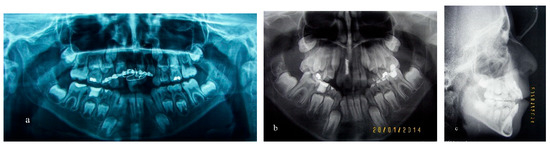

Treatment of an Avulsed and Ankylosed Incisor through Single Tooth Alveolar Osteotomy and Conventional Orthodontic Mechanisms

2. Materials and Methods

3. Results